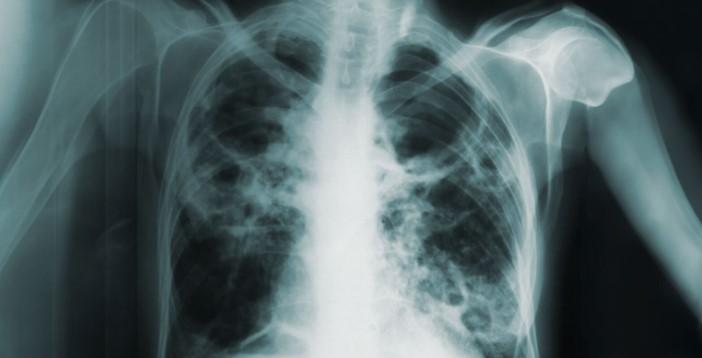

– وجود باکتری سل در خلط، تأیید کننده وجود بیماری سل است. - 3. رادیوگرافی ریه (Chest X-ray):

– این آزمایش تصویربرداری از قفسه سینه فرد را انجام میدهد.

– در این تصاویر، ضایعات و آسیبهای ریوی ناشی از سل قابل تشخیص هستند. - 4. آزمایش مولکولی (Molecular test):